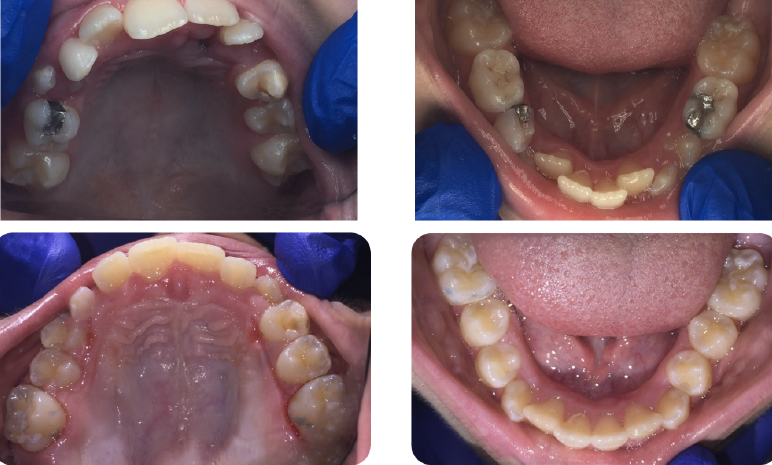

Fig 1. An 11-year-old girl presented with severe crowding and maxillary and mandibular hypoplasia. Previous recommendation was serial extraction of the remaining primary teeth and

the four bicuspids. The patient presented to the author’s practice office seeking alternative treatment for phase 1 utilizing expansion.

Fig 3. Pretreatment (top panels) and peri-treatment (bottom panels) intraoral photographs.

Figure 3